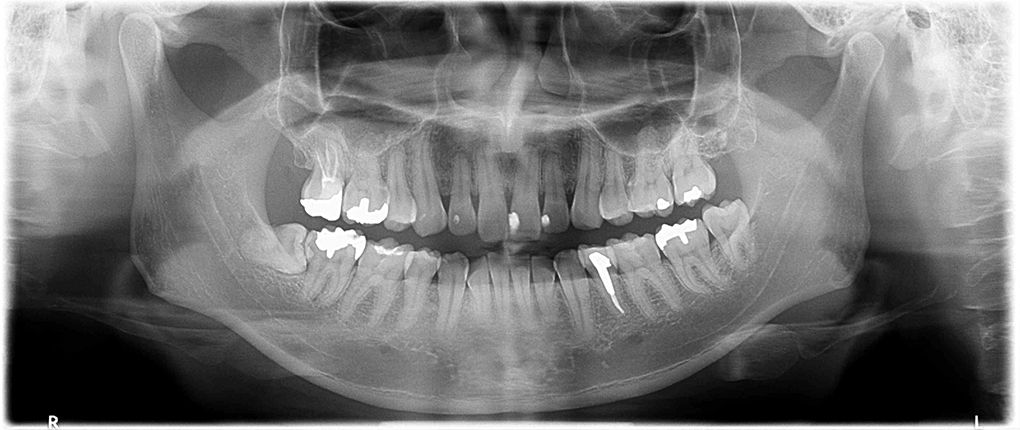

レントゲン撮影(ご希望の場合のみ)

レントゲン撮影を行うことで、肉眼では確認できない歯茎の中の骨の状態や、これから生えてくる永久歯の状態、親知らずの状態が分かります。治療の開始時期や治療の必要性などが判断出来ます。